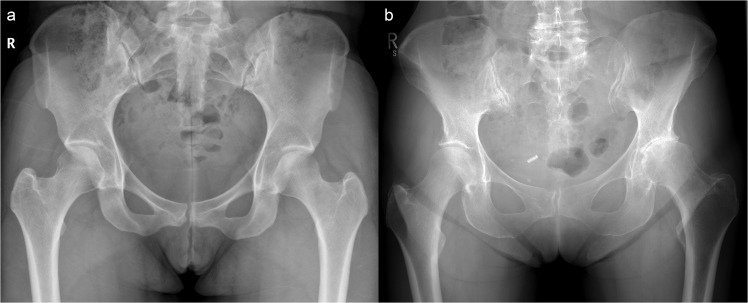

The ability to map JSW in 3D also delivers an opportunity to revisit a rarely considered phenomenon. Experience from our clinical practice has shown that one hip tends to degenerate prior to the opposite, as demonstrated in Fig. 1. To the best of our knowledge, only two previous studies have specifically commented on radiographic JSW asymmetry21,22. The first, by Reis et al. in 1999, looked at the difference in superior JSW in 171 individuals without hip pain or radiographic evidence of disease, concluding that side differences in JSW greater than 0.7 mm at the superior joint space strongly suggested pathological joint narrowing. In 2004, Lequesne et al. then examined the same superior locations for radiographic minimum JSW and concluded that asymmetry was rare, seeing a difference greater than their limits of agreement (1.45 mm) in only 13 out of 221 subjects (5.9%)22. Using the opposite hip could provide an approach for a single time-point assessment of osteoarthritis risk from this internal comparison.

Figure 1.

Anteroposterior radiographs of the pelvis in two adult females. The individual in (a) has no evidence of radiological osteoarthritis on either side (KL grade 0); however, the individual in (b) has marked disease asymmetry, with no radiological disease in the right hip (KL grade 0), but moderate disease in the left (KL grade 3).